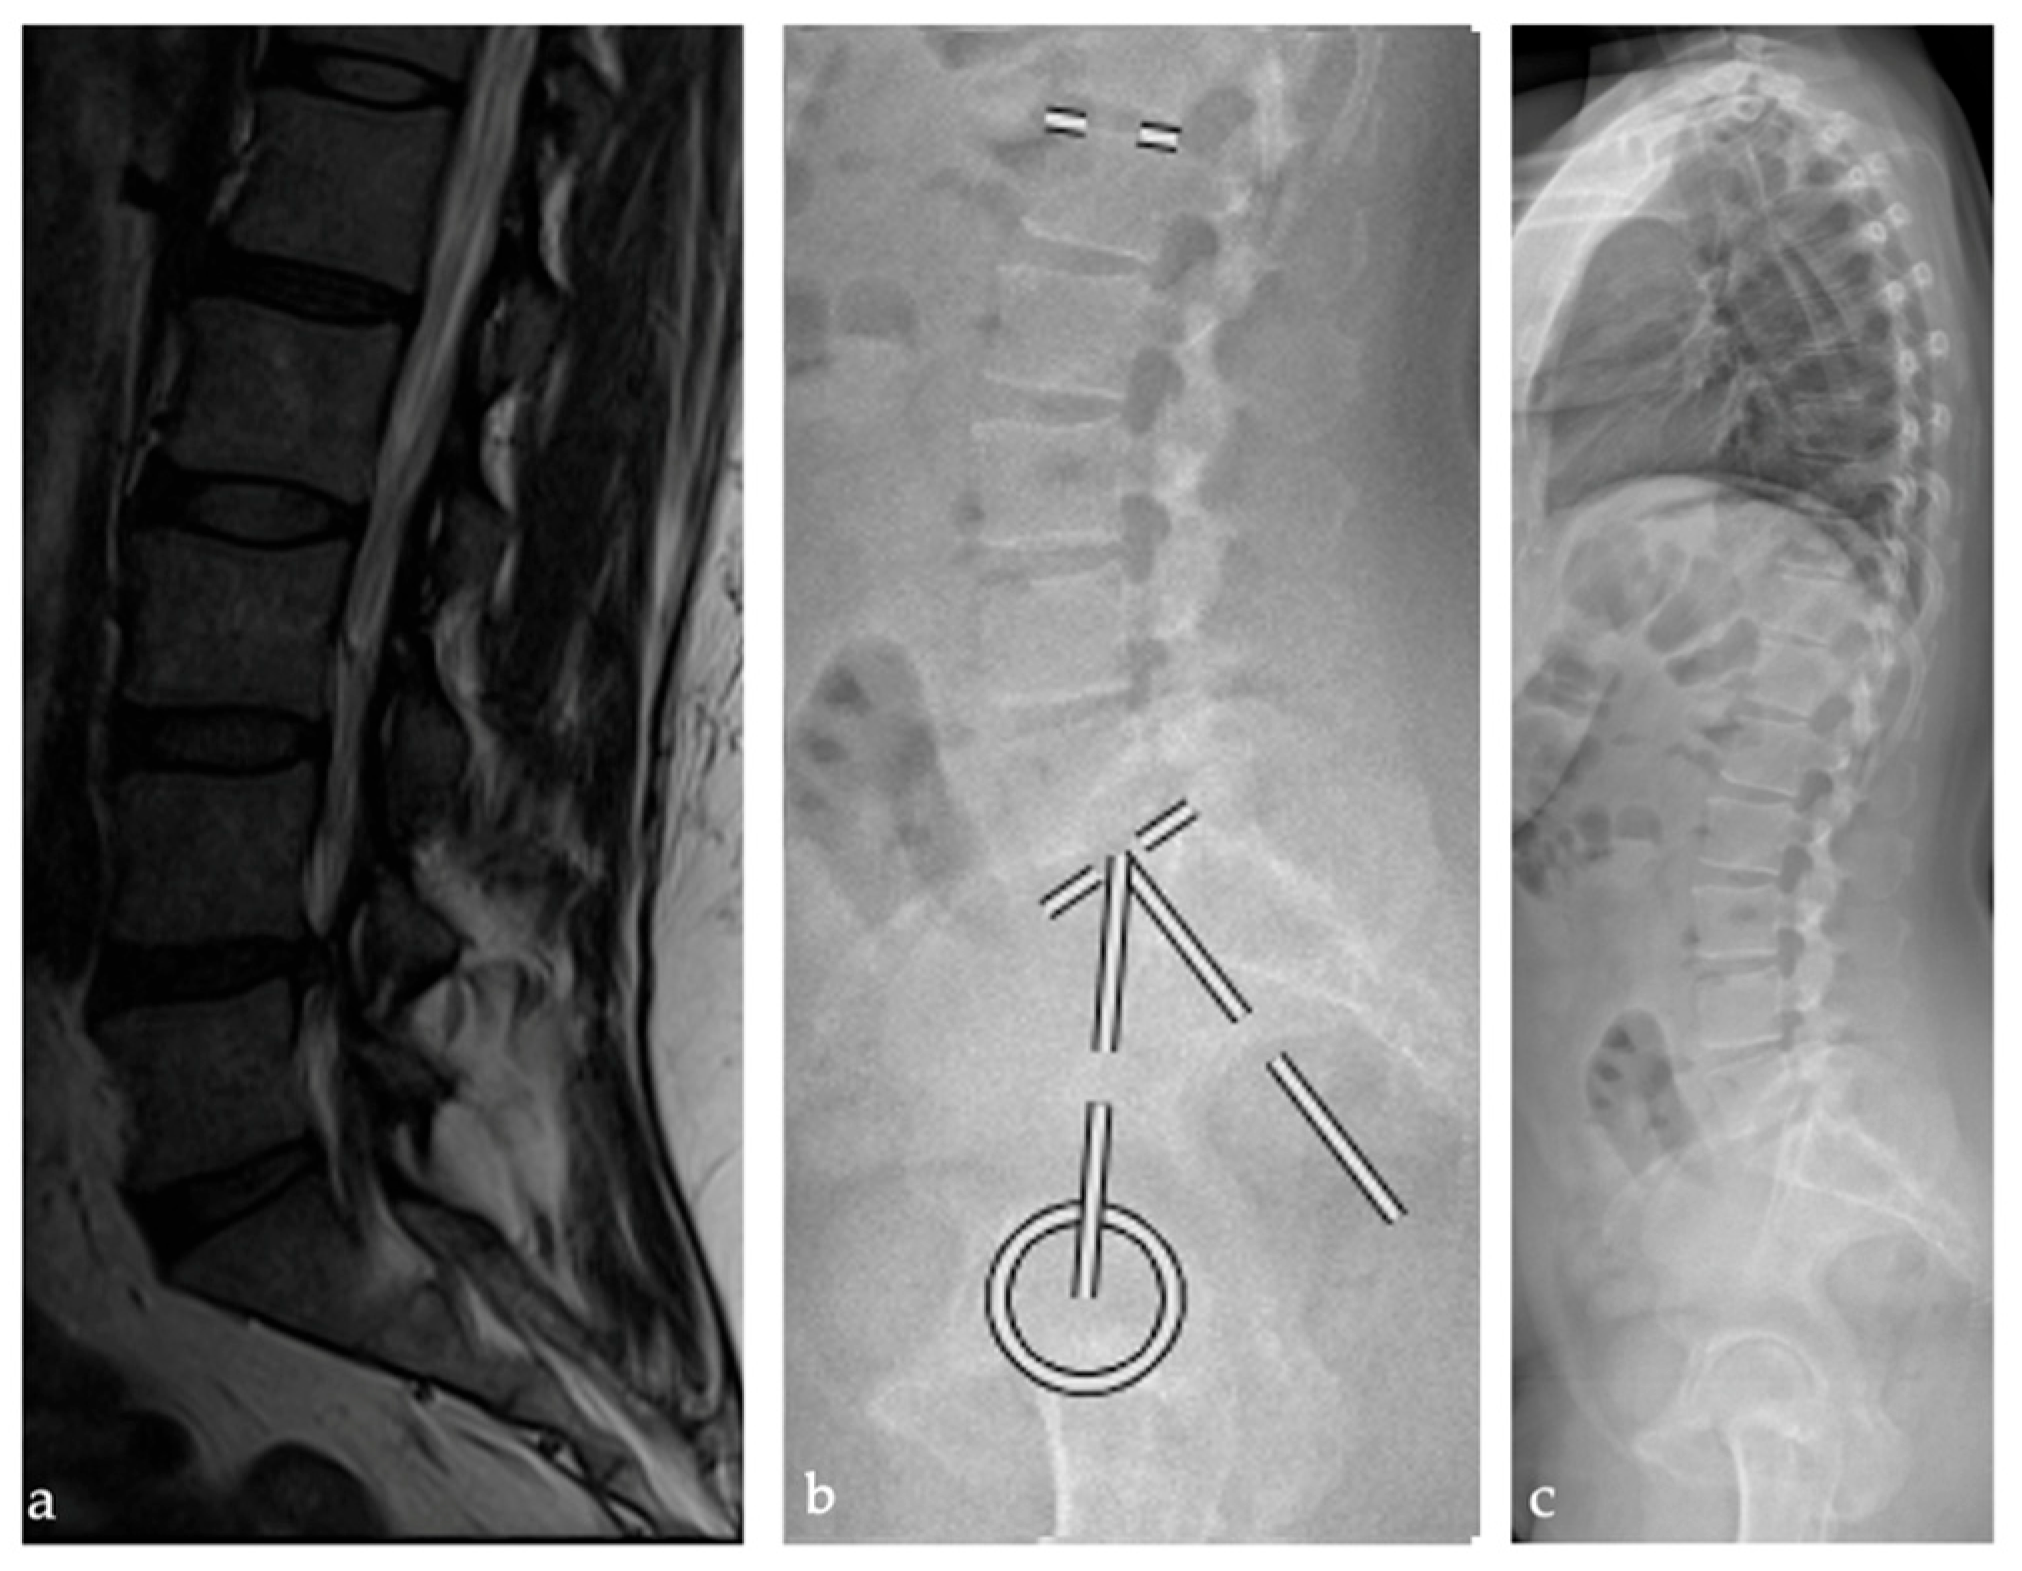

2.2. Radiographic Analysis